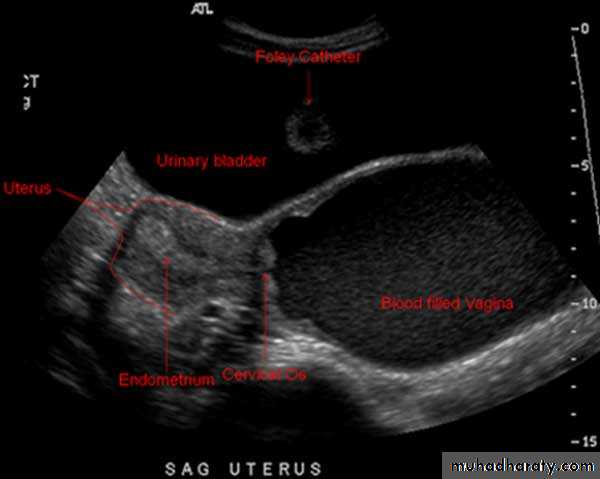

• Uterus

• Reconstructed coronal view of the uterus demonstrating cornuas (arrow) and cervix, with a normal uterine contour• Normal Uterus

• Planar views of normal uterus using volume contast imagingNormal Uterus

Normal Uterus in longitudinal viewUterine Pathology